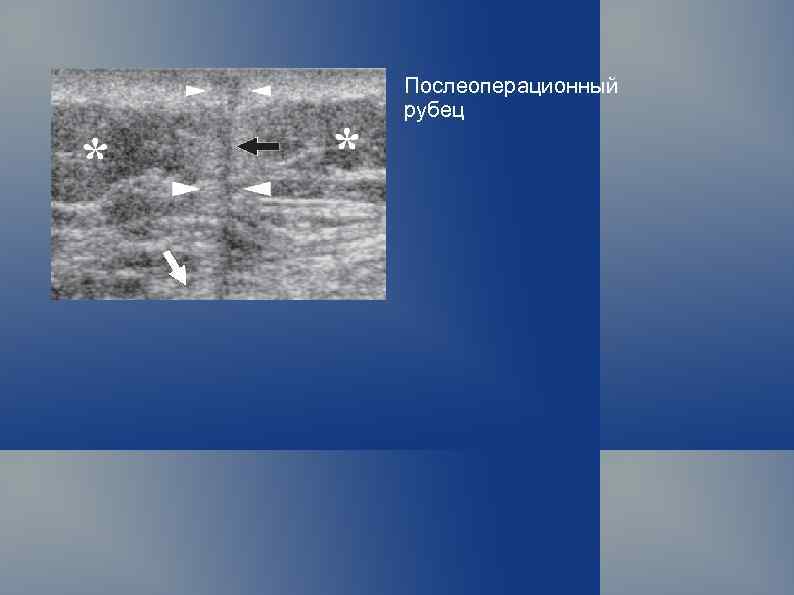

Послеоперационный рубец